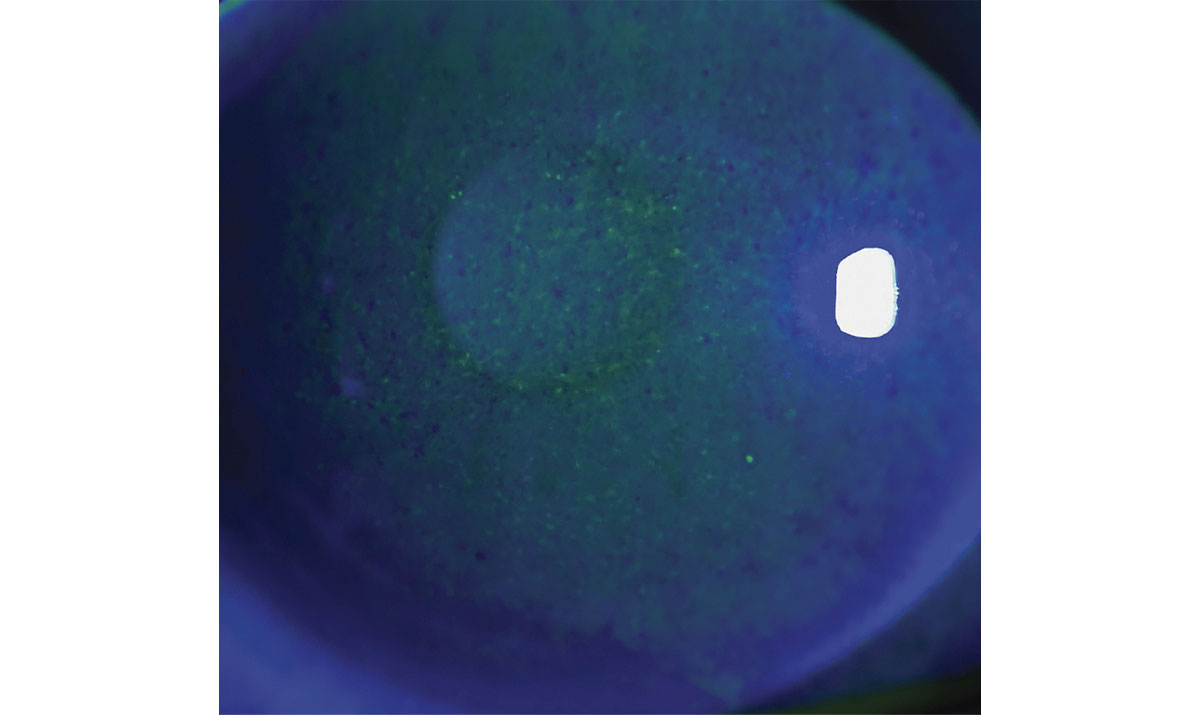

Figura 2. Fotografía con lámpara de hendidura de un paciente con ojo seco, obtenida con iluminación directa.

Foto: Kevin M. Miller, MD.

Figura 3. Imagen con luz azul cobalto del ojo mostrado en la figura 2 después de la instilación de fluoresceína, que evidencia queratopatía punteada superficial secundaria al ojo seco.